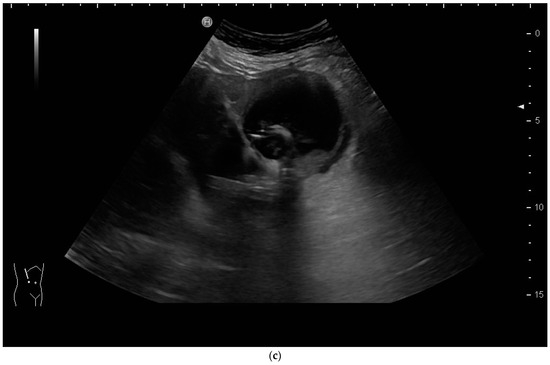

The aims of PGBD are the relief of symptoms and the disappearance of inflammation. If these criteria are met, the drainage can be removed. After pre-existing GB perforation, the integrity of the gallbladder wall should be documented. This can be performed very well by the injection of US-contrast agents (Figure 12 and Figure 13) [80].

Figure 12.

After injection of one drop of SonoVue® diluted in 10 mL sodium chloride 0.9% via drainage, gallbladder perforation and leakage can be excluded. Only the drain and the gall bladder lumen show enhancement (left side: low-MI-mode, right side: conventional grey-scale image).

Figure 13.

Gall bladder perforation. After injection of diluted US-contrast agent via the drain, contrast media appears at the lower liver surface. The drain was left in place for a few more days until surgery could be performed.

After the injection of one drop of SonoVue®, e.g., diluted in 10 mL sodium chloride 0.9% via the drain, gallbladder perforation and leakage can be excluded when only the drainage and the gall bladder lumen show enhancement, and no extravasation is observed.